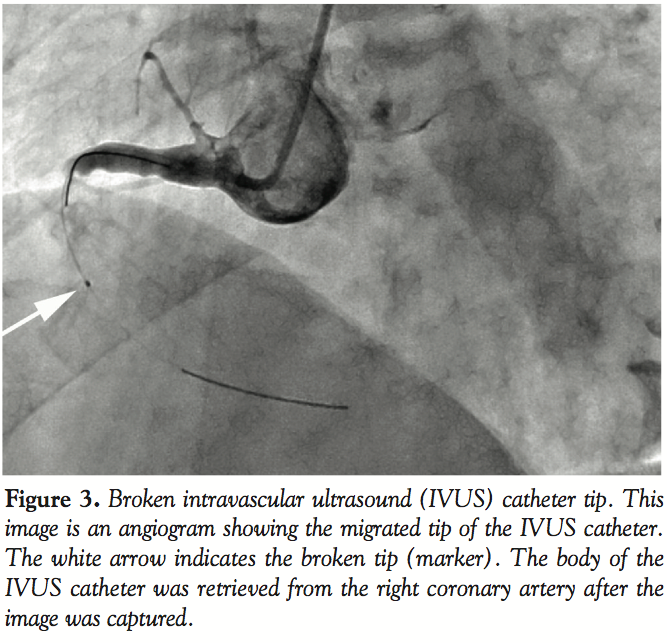

We captured plaque images and decided to perform direct stenting with a 4.0 mm bare-metal stent. After the examination, we removed the catheter with some difficulty, but the tip of the IVUS catheter (marker) broke and remained in the distal part of the narrowing of the RCA (Figure 3). We attempted to dilate the narrowing with a balloon catheter and a stent, so that a retrieval device could be introduced into the narrowed artery to remove the broken tip. When balloon angioplasty with a

3.0 mm balloon catheter was performed, the tip shifted to the middle of the RCA. A 4.0 mm bare-metal stent was successfully implanted into the proximal RCA and dilated the narrow part. We first tried to remove the tip with a conventional gooseneck snare. However, this snare pushed the tip further into the AV branch, and we could not retrieve it from the AV branch with a conventional gooseneck snare (Figure 4).